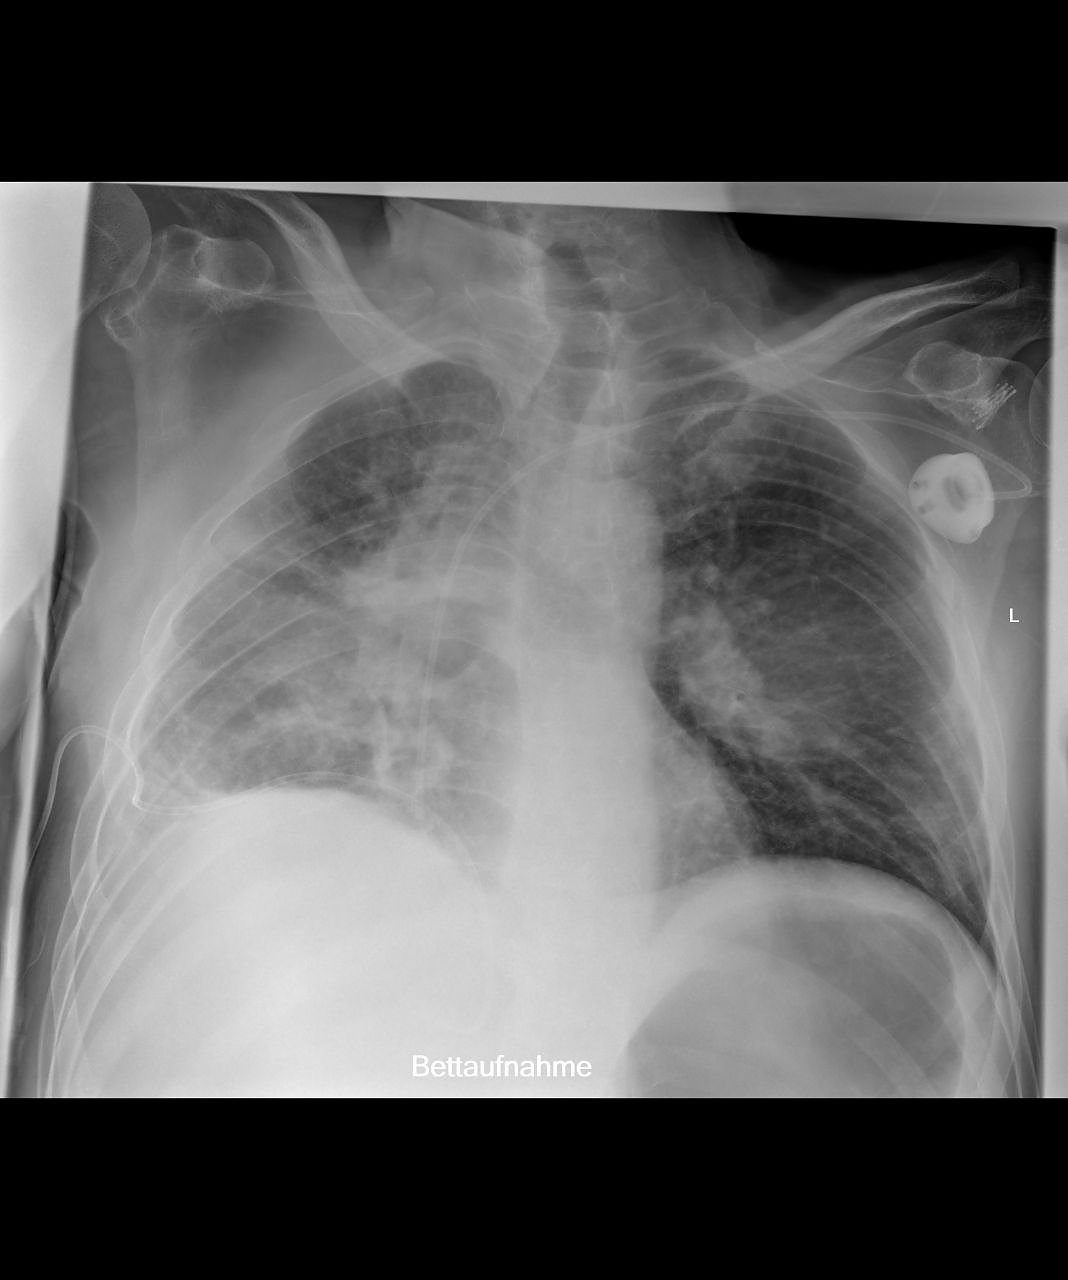

Außerdem ermöglicht die neue Röntgeneinheit die Anfertigung von Ganzbein- und Ganzwirbelsäulenaufnahmen direkt digital mit nachfolgender elektronischer fehlerfreier und versatzfreier Zusammenfügung der Bilddatensätze. Diese Ganzbein- und Ganzwirbelsäulenaufnahmen sind für die Planung endoprothetischer Versorgungen wesentlich. Darüber hinaus sind sie von großem Nutzen in der Therapieabschätzung bei Skoliose oder anderer Fehlstellungen der Wirbelsäule. Auch bezüglich der Bildqualität von im Liegen anzufertigenden Aufnahmen bietet das System wesentliche Vorteile. Häufig werden heutzutage Liegendröntgenaufnahmen mit Verwendung eines Rasters durchgeführt, um die sonst bildqualitativ beeinträchtigende Streustrahlung zu verringern. Die Röntgendosis steigt aber durch diese Rastertechnologie. Alternativ muss man die sonst schlechtere Bildqualität bei Liegendaufnahmen in Kauf nehmen, was die Befundung beeinflussen kann. Nach unserer Kenntnis erstmalig in Thüringen verfügbar, ist nun für diese schwerkranken Patienten (die deshalb nur im Liegen geröntgt werden können) das sogenannte Sky Flow Processing”, erklärt der Chefarzt.

Hierbei wird ein Algorithmus zur Nachverarbeitung der Bilddatensätze angewandt, der streustrahlungsbedingte Effekte des Röntgenbildes automatisch erkennt und durch einen zusätzlichen nachverarbeitenden Filter korrigiert. Die Folge ist eine deutlich verbesserte Bild- und damit verbunden Befundungsqualität, sodass nach bisherigen Studien die Bildqualität ohne Raster mit Sky Slow Technologie der Bildqualität mit Raster entspricht. Auch hierfür ist das radiologische Institut des Südharz Klinikums wiederum Referenzzentrum. Erste interessierte Radiologen haben bereits einen Besuchstermin am Südharz Klinikum vereinbart, um diese neue Nachverarbeitungsoption in praktischer Anwendung zu sehen.